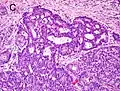

![]() Gleason grade — Lower grades are associated with small, closely packed glands. Cells spread out and lose glandular architecture as grade increases. Gleason score is calculated from grade as described in the text. |

A pathologist microscopically examines the biopsy specimen for certain "Gleason" patterns. These Gleason patterns are associated with the following features:

- Pattern 1 - The cancerous prostate closely resembles normal prostate tissue. The glands are small, well-formed, and closely packed. This corresponds to a well differentiated carcinoma.

- Pattern 2 - The tissue still has well-formed glands, but they are larger and have more tissue between them, implying that the stroma has increased. This also corresponds to a moderately differentiated carcinoma.

- Pattern 3 - The tissue still has recognizable glands, but the cells are darker. At high magnification, some of these cells have left the glands and are beginning to invade the surrounding tissue or having an infiltrative pattern. This corresponds to a moderately differentiated carcinoma.

- Pattern 4 - The tissue has few recognizable glands. Many cells are invading the surrounding tissue in neoplastic clumps. This corresponds to a poorly differentiated carcinoma.

- Pattern 5 - The tissue does not have any or only a few recognizable glands. There are often just sheets of cells throughout the surrounding tissue. This corresponds to an anaplastic carcinoma.

In the present form of the Gleason system, prostate cancer of Gleason patterns 1 and 2 are rarely seen. Gleason pattern 3 is by far the most common.